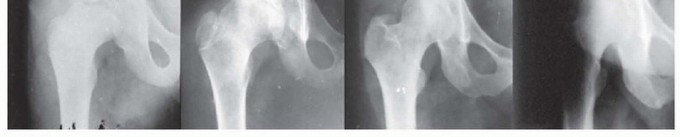

FIG 4 • Anteroposterior (AP) radiographs of the hip of a patient with Perthes disease in whom the deformed femoral head was treated by a labral support (shelf) procedure. There is remodeling of the femoral epiphysis, widening of the acetabulum, and resolution of the shelf.

*

OUTCOMES

Domzalski et al6 reported the results of 49 consecutive patients treated by the labral support (shelf) procedure for Perthes disease.

The procedure has a combined effect to prevent subluxation, to stimulate additional growth of the lateral rim of the acetabulum in a vertical dimension, and to provide temporary osseous containment until the shelf resorbs with time in a manner that is beneficial for preventing impingement of the femoral neck and greater trochanter on the shelf (

FIG 4

).